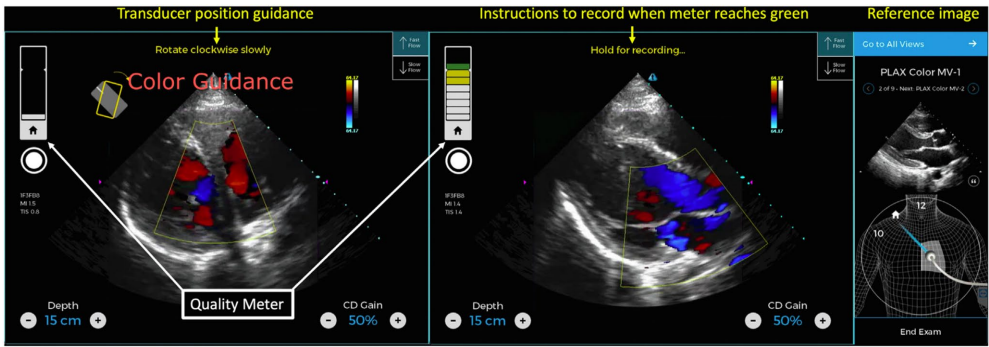

人工智能(AI)在心血管医学中的应用正重塑诊疗标准,而便携式床旁超声(POCUS)因其即时成像能力成为关键载体。然而,操作者技能差异限制了其普及。AI的介入通过实时引导探头定位、自动化图像分析(如心包积液检测仅需57毫秒),为新手与资深医师提供均质化支持,显著提升诊断效率。

卷积神经网络(CNN)擅长处理高维超声数据,而生成式AI(如大型语言模型)可标准化报告生成。研究显示,AI辅助系统能指导护士获取诊断级图像,医学学生经实时反馈后亦可准确评估LVEF。深度学习模型AutoLV可在8秒内完成LVEF测算,且无人工变异性。更复杂的应用包括应激超声中冠脉疾病的AI识别,其准确率媲美经验丰富的医师。

聚焦心脏超声(FCU)虽简化了心脏评估(如心包积液、心室功能),但对瓣膜病变等复杂病理敏感度不足。AI通过以下方式弥补缺陷: